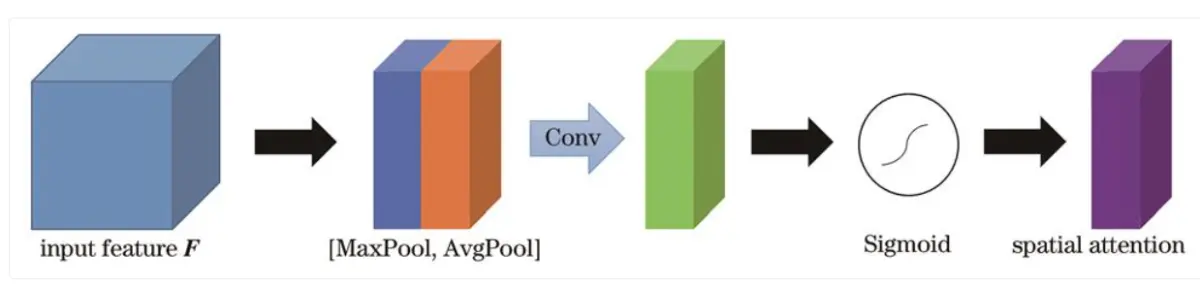

# 空间注意力模块 (Spatial Attention)

class SpatialAttention(tf.keras.layers.Layer):

def __init__(self):

super(SpatialAttention, self).__init__()

self.conv = tf.keras.layers.Conv2D(1, 7, padding='same', activation='sigmoid')

def call(self, x):

avg_feat = tf.reduce_mean(x, axis=3)

max_feat = tf.reduce_max(x, axis=3)

concat = tf.concat([avg_feat, max_feat], axis=3)

sa = self.conv(concat)

return x * sa

10.卷积块注意力模块

卷积块注意力模块结合了通道注意力机制与空间注意力机制,相较于只关注通道域的SE模块,CBAM在通道域和空间域两个维度推算注意力图,可筛选出更重要的语义特征,因此可以取得更好的效果,具体结构如图所示。

首先将特征图输入到通道注意力模块中得到对应通道的权重,得到加权结果后将加权后的特征图输入空间注意力模块中得到对应权重,加权后输出特征图,计算方法表示为: